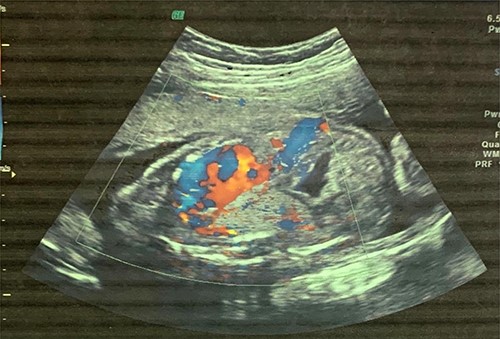

A 6-month-old male baby who was found to have fetal adenomatoid malformation from a prenatal ultrasound (US) done at 20 weeks’ gestation and polyhydramnios at 30 weeks’ gestation (Fig. 1) is reported. The mass measured 4.7 × 4.1 × 3.5 cm with no evidence of systemic feeding artery, associated anomalies or hydrops at 24 weeks. Cesarean delivery was done at 38 weeks’ gestation for severe polyhydramnios. He spent first 3 weeks at the neonatology unit with respiratory distress and again on sixth week of life for pneumonia. A chest computed tomography (CT) scan (Fig. 2) at 2 weeks showed a wedge-shaped homogenously enhancing mass measuring 4.8 × 2.8 × 1.8 cm in the left lower lobe with an aberrant arterial branch from the descending thoracic at T12. Cardiothoracic surgery reviewed and maintained patient for surgery. He had normal preoperative laboratory work-up and underwent aberrant artery ligation and resection of the sequestrated lung via standard left posterolateral thoracotomy.

Fetal US at 20 weeks’ gestation showing an echogenic mass in the left lower lobe, which was initially thought to be congenital pulmonary adenomatoid malformation.